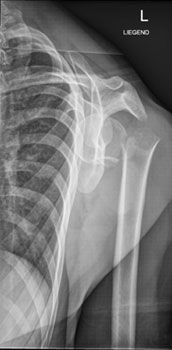

Die Röntgenaufnahme der Schulter in zwei Ebenen ist die Untersuchung der Wahl zur Beurteilung der Knochenstrukturen und der Gelenkstellung.

Hier sehen Sie die Aufnahmen im vorliegenden Fall:

Schulter ap